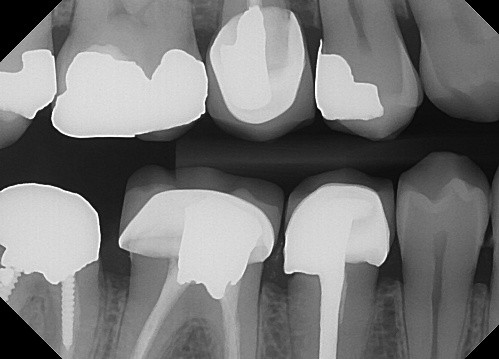

12 / 50

12. (Select ONE OR MORE correct answers)

The radiograph shows evidence of

13 / 50

13. (Select ONE or MORE correct answer)

Which of the following is true regarding dental implant at site 2.6?

14 / 50

14. (Select ONE OR MORE correct answer)

Which of the following is true regarding dental implant at site 3.6?